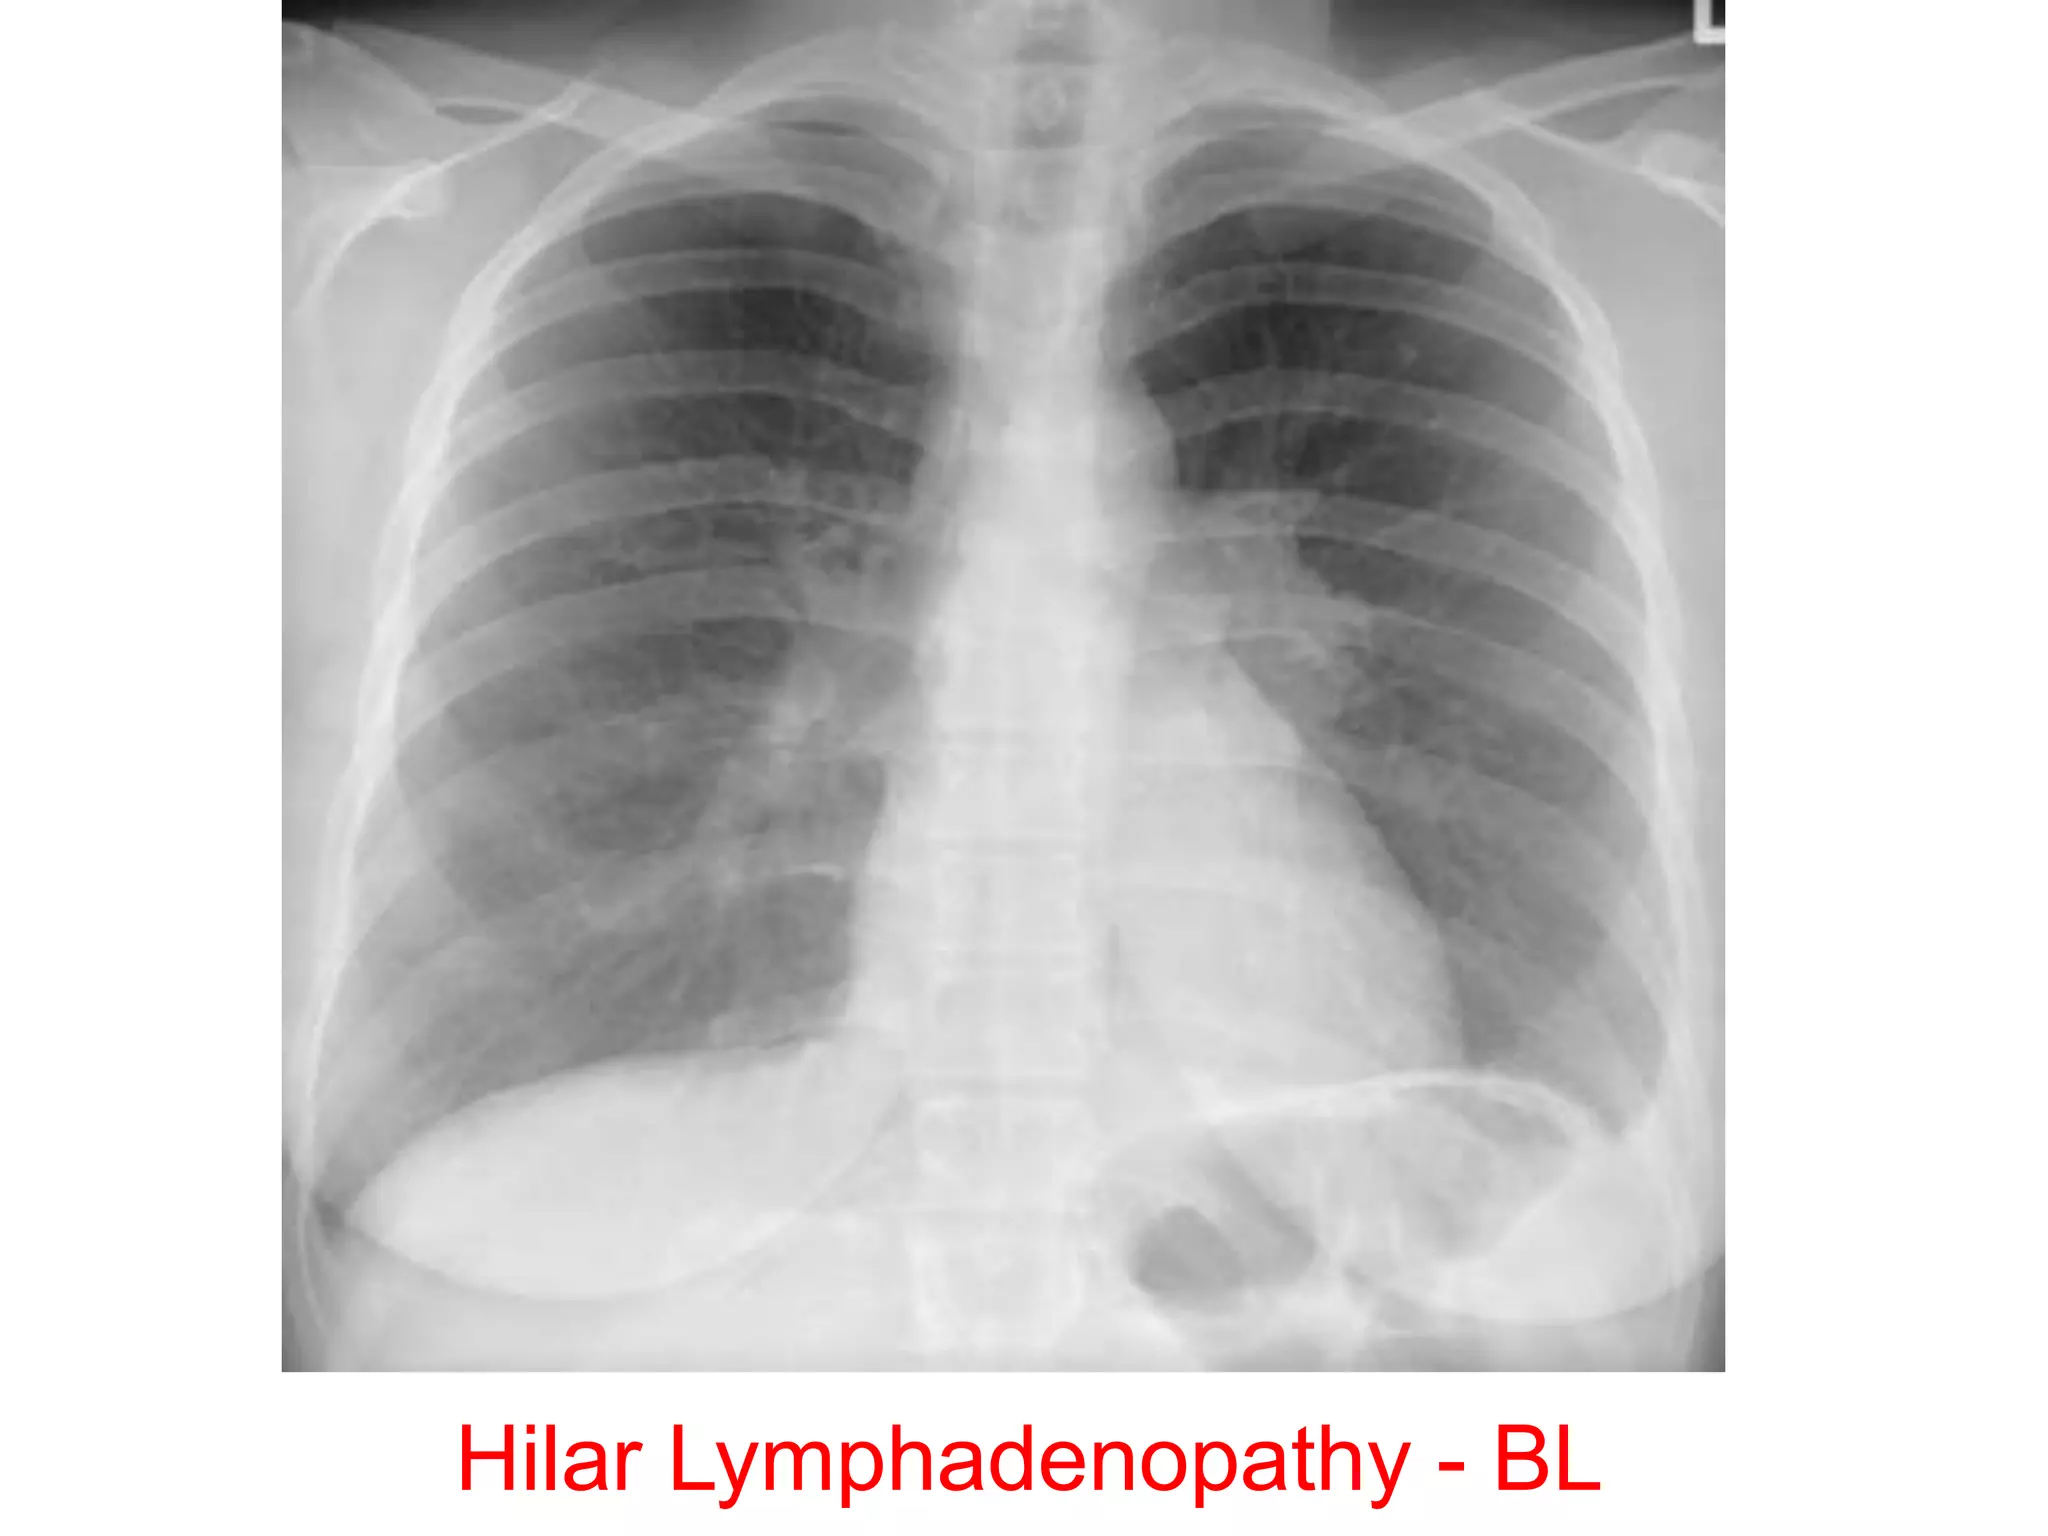

Hilar Lymphadenopathy - BL

69154 slides NormalHilar and Mediastinal Lymphadenopathy

69154 slides NormalHilarand Mediastinal Lymphadenopathy Diagnosis? 69